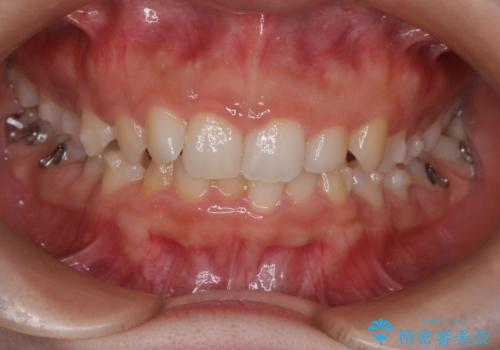

インビザラインで整える深い噛み合わせ

- 患者様は、ディープバイト(深い噛み合わせ)と、咬合平面の左下がりが気になるとのことでご来院されました。診断の結果、非抜歯で治療可能と判断し、透明なマウスピース型矯正装置「インビザライン」を用いる方針としました。治療では、歯列全体の調整を行いながら、咬合平面の水平化を重点的に進める計画を立案しました。2年間で計画的にマウスピースを交換し、左右のバランスと噛み合わせの改善を目指しました。

ディープバイトの矯正は、噛み合わせが深くなりがちなため、細心の注意を払いながら進める必要があります。本症例では、奥歯の高さを調整しつつ前歯の噛み合わせを浅くすることで、全体の咬合バランスを整えました。また、咬合平面の左下がりを修正する過程で、歯列に不均等な力がかからないよう、インビザラインのアタッチメント配置を最適化しました。患者様には装着時間を守っていただき、治療が計画通り進むよう協力をお願いしました。治療終了後には、リテーナーを装着して安定性を確保しました。